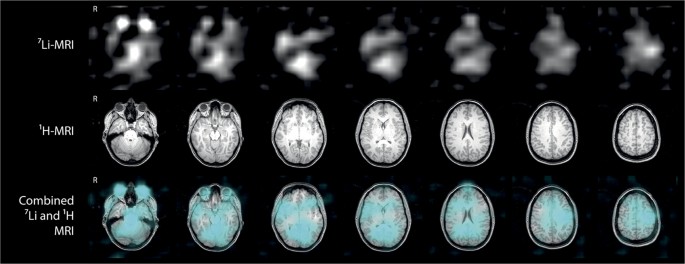

Heterogeneity of lithium distribution across the brain was observed in all subjects. Figure 2 shows 7Li b-SSFP images and corresponding 1H MRI axial slices from one individual (subject B), demonstrating heterogeneous distribution of lithium throughout the brain. Figure 3 shows individual 7Li b-SSFP images and the corresponding 1H MRI axial slice at the level of the head of the caudate nucleus from each of the eight subjects, with the distribution seen to differ between subjects. The average COV of 7Li b-SSFP signal intensity was 27.9 ± 3.6%, numerically confirming that brain lithium distribution is heterogeneous.

7Li b-SSFP MRI in a single subject. The 7Li-MRI dataset (upper row) was acquired in 8 min and is presented with corresponding 1H-MRI axial images (middle row). The combined images (lower row) show 7Li b-SSFP MRI (in cyan) overlaid on 1H-MRI images. The distribution of lithium in the brain is heterogeneous and the greatest signal intensity arises from the orbits